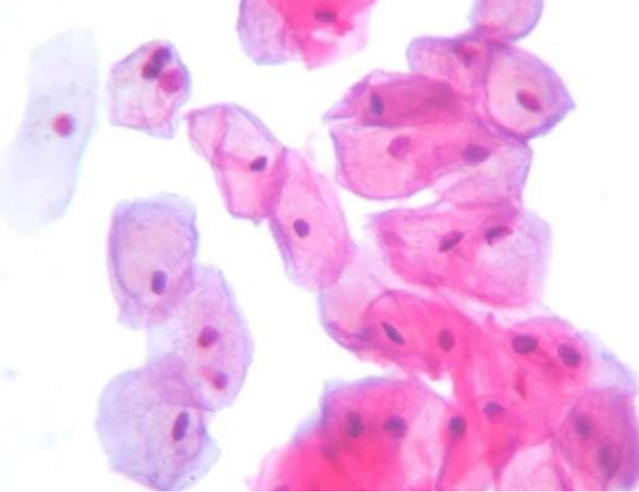

CITOLOGÍA FROTIS VAGINAL

- CÉLULAS SUPERFICIALES

- CÉLULAS INTERMEDIAS

- CÉLULAS PARABASALES

- CÉLULAS BASALES